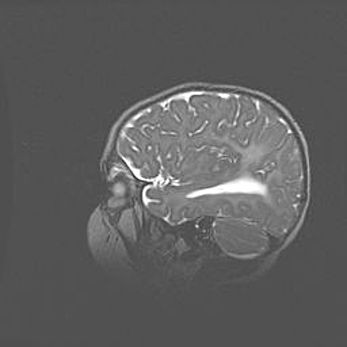

Наружная гидроцефалия с возможной атрофией височных областей.

Возраст: 28 дней

Вес: 3670 г

Пол: мужской

Окружность головы: 38 см

Срок гестации: 40 недель

Гидроцефалия головного мозга у новорожденных – это заболевание, которое характеризуется скоплением избыточного количества спинномозговой жидкости в желудочковой системе головного мозга в результате затруднения её перемещения от места выработки к месту поглощения в кровеносную систему или вследствие нарушения абсорбции. При открытой наружной форме гидроцефалии у новорожденных расширяются и переполняются субарахноидные пространства.

При нормотензивных  формах,  которые,  как  правило,  являются  следствием  перенесенных ишемических  повреждений  паренхимы  мозга,  возможно  сочетание микроцефалии  с нормотензивной гидроцефалией. В основе данных изменений лежит атрофия больших полушарий с преимущественной  локализацией  в  лобно-височных  областях.